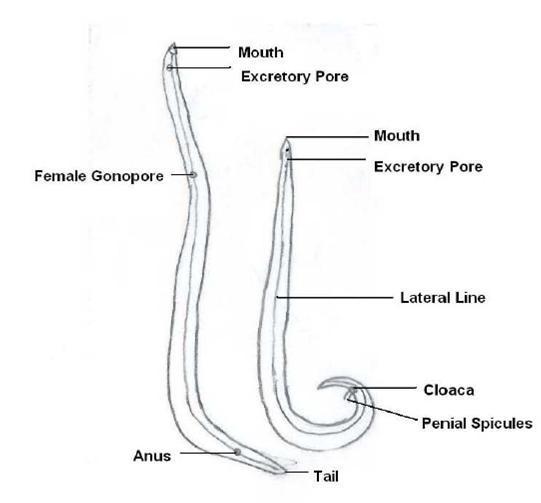

Nematoda- Ascaris lumbricoides

Vector is anopheles mosquito (female mosquito)

causes more virulant malaria